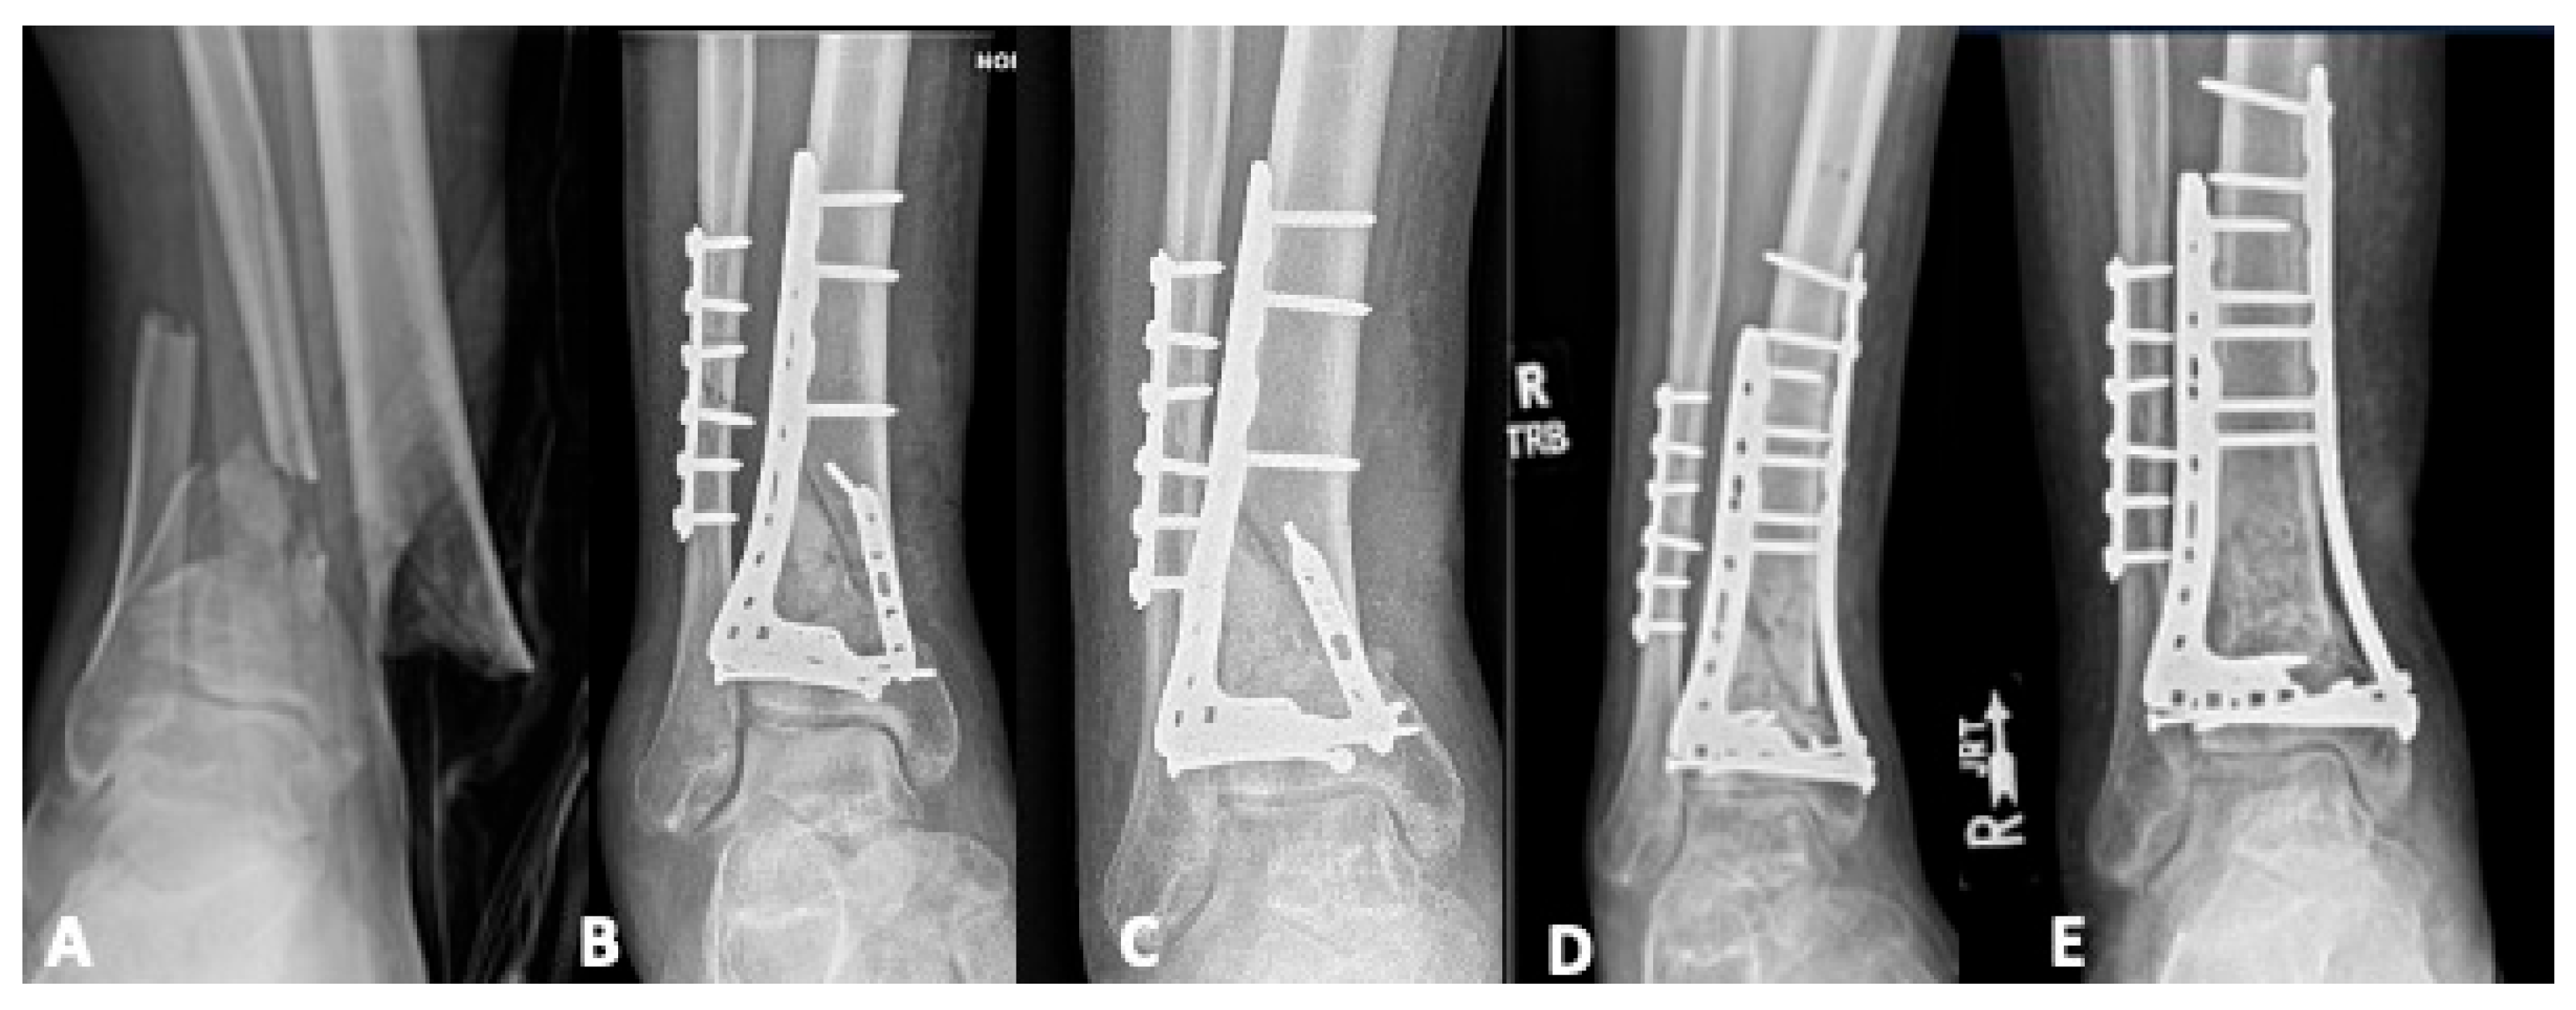

4.3. Malunion

5.1. Revision Operative Fixation